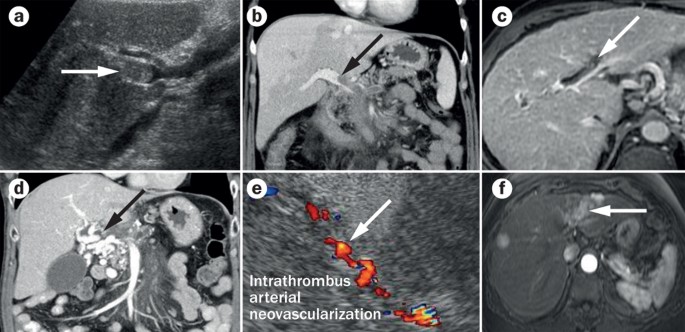

Imaging Findings Of Portal Vein Thrombosis A An Ultrasound Study Of Download Scientific Diagram